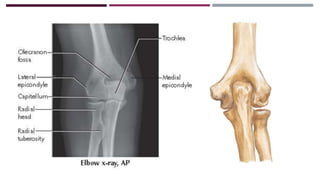

IMAGENOLOGÍA

RADIOGRAFÍA

Obtenida antes de la

reducción

Obtenida después de la

RADIOGRAFÍA Obtenida antes dela reducción Obtenida después de la reducción